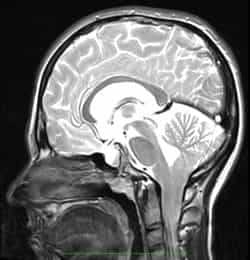

Следует отметить, что МСКТ и КТ головного мозга при хорошей визуализации костных структур краниовертебрального перехода не позволяют достаточно точно судить о мягкотканных образованиях задней черепной ямки. Поэтому единственным достоверным методом диагностики аномалии Киари на сегодняшний день является магнитно-резонансная томография. Ее проведение требует обездвиженности пациента, поэтому у маленьких детей она проводится в состоянии медикаментозного сна. Кроме МРТ головного мозга для выявления менингоцеле и сирингомиелических кист необходимо также проведение МРТ позвоночника, особенно его шейного и грудного отделов. При этом проведение МРТ исследований должно быть направлено не только на диагностику аномалии Киари, но и на поиск других аномалий развития нервной системы, которые часто с ней сочетаются.

Точная диагностика аномалии стала возможна благодаря использованию МРТ, посредством которой врач может определить и костные пороки, и варианты развития самого мозга, его сосудов, уровень расположения отделов относительно черепных костей, их размеры, объем задней черепной ямки и ширину большого затылочного отверстия. МРТ можно считать единственным точным и самым достоверным методом выявления патологии.

МРТ требует обездвиживания пациента, который должен какое-то время спокойно лежать на столе аппарата. У детей с этим могут возникнуть значительные трудности, поэтому исследование проводят в состоянии медикаментозного сна. Для поиска сочетанных пороков спинного мозга и позвоночника исследуют также эти отделы позвоночного столба.